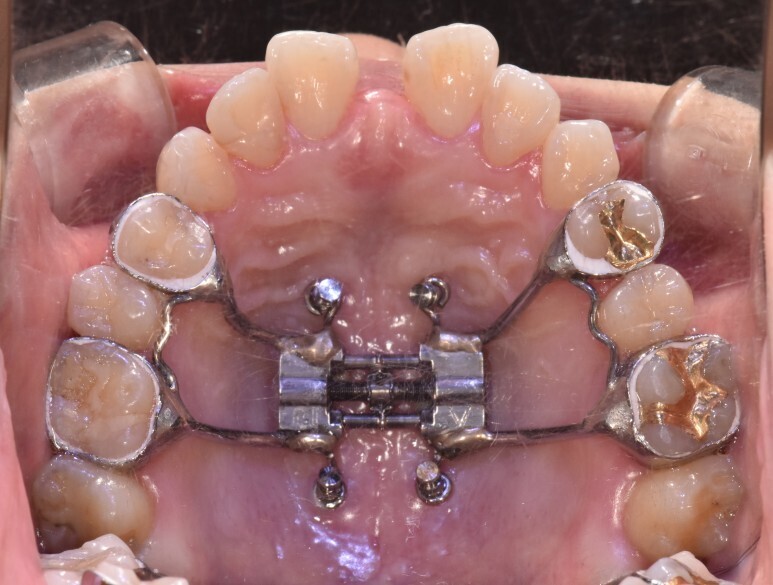

좀더 강한 힘을 치아에 가하는 RPE같은 확장장치를 사용하여 좌우측 구개골을 벌리게 됩니다.

초기사춘기에는 일주일에 한두번 나사를 돌리는 slow palatal expansion으로 윗턱을 확장할 수 있으나 후기사춘기일수록 하루에 두번씩 돌리는 rapid palatal expansion을 해야 윗턱을 좌우로 벌릴 수 있습니다.

나이가 들수록 윗턱을 벌리는 데 더 강력한 힘이 필요하다라는 뜻입니다.

이젠 손잡이를 바꾸어야합니다(어금니-> 미니스크류)

좌우측 구개골을 벌리는 데 있어 상악어금니보다 더 강력한 손잡이가 필요합니다.

바로 입천장의 구개골에 직접 미니스크류를 식립하여 윗턱을 벌리는 손잡이로 쓰는 것입니다.

이것을 MARPE라고 부릅니다.